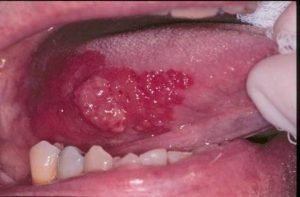

الطلاوة الحمراء

إنه اللون الأحمر للجروح في الطلوان.